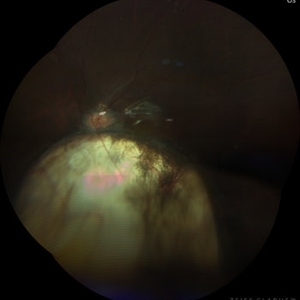

Total Rhegmatogenous retinal detachment with lattice degeneration & Vitreous haemorrhage

Jul 31 2023 by Harsh Vardhan Singh, MS

72-year male presented PVD induced total retinal detachment with vitreous hemorrhage

Photographer: Dr Harsh Vardhan Singh, AIIMS, Guwahati

Imaging device: Zeiss Clarus 700

Condition/keywords: chronic retinal detachment, hemorrhage, rrd